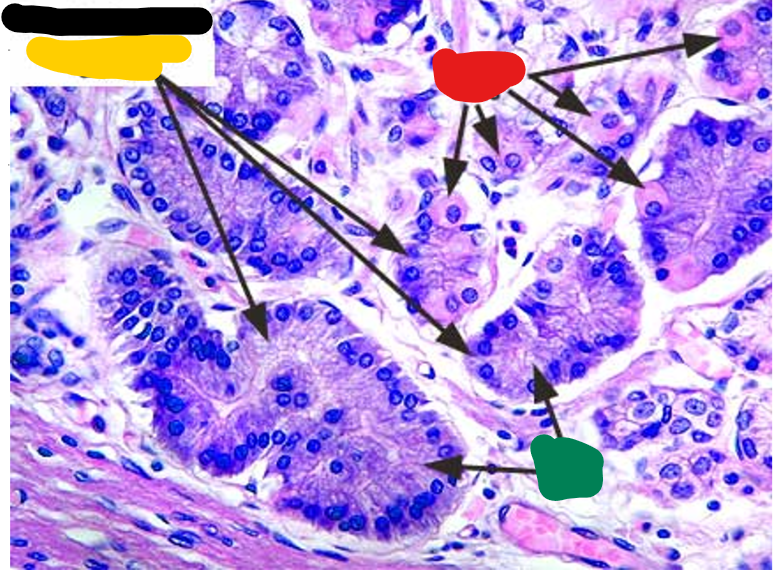

the arrows point to

Paneth cell

Brunner’s or duodenal glands